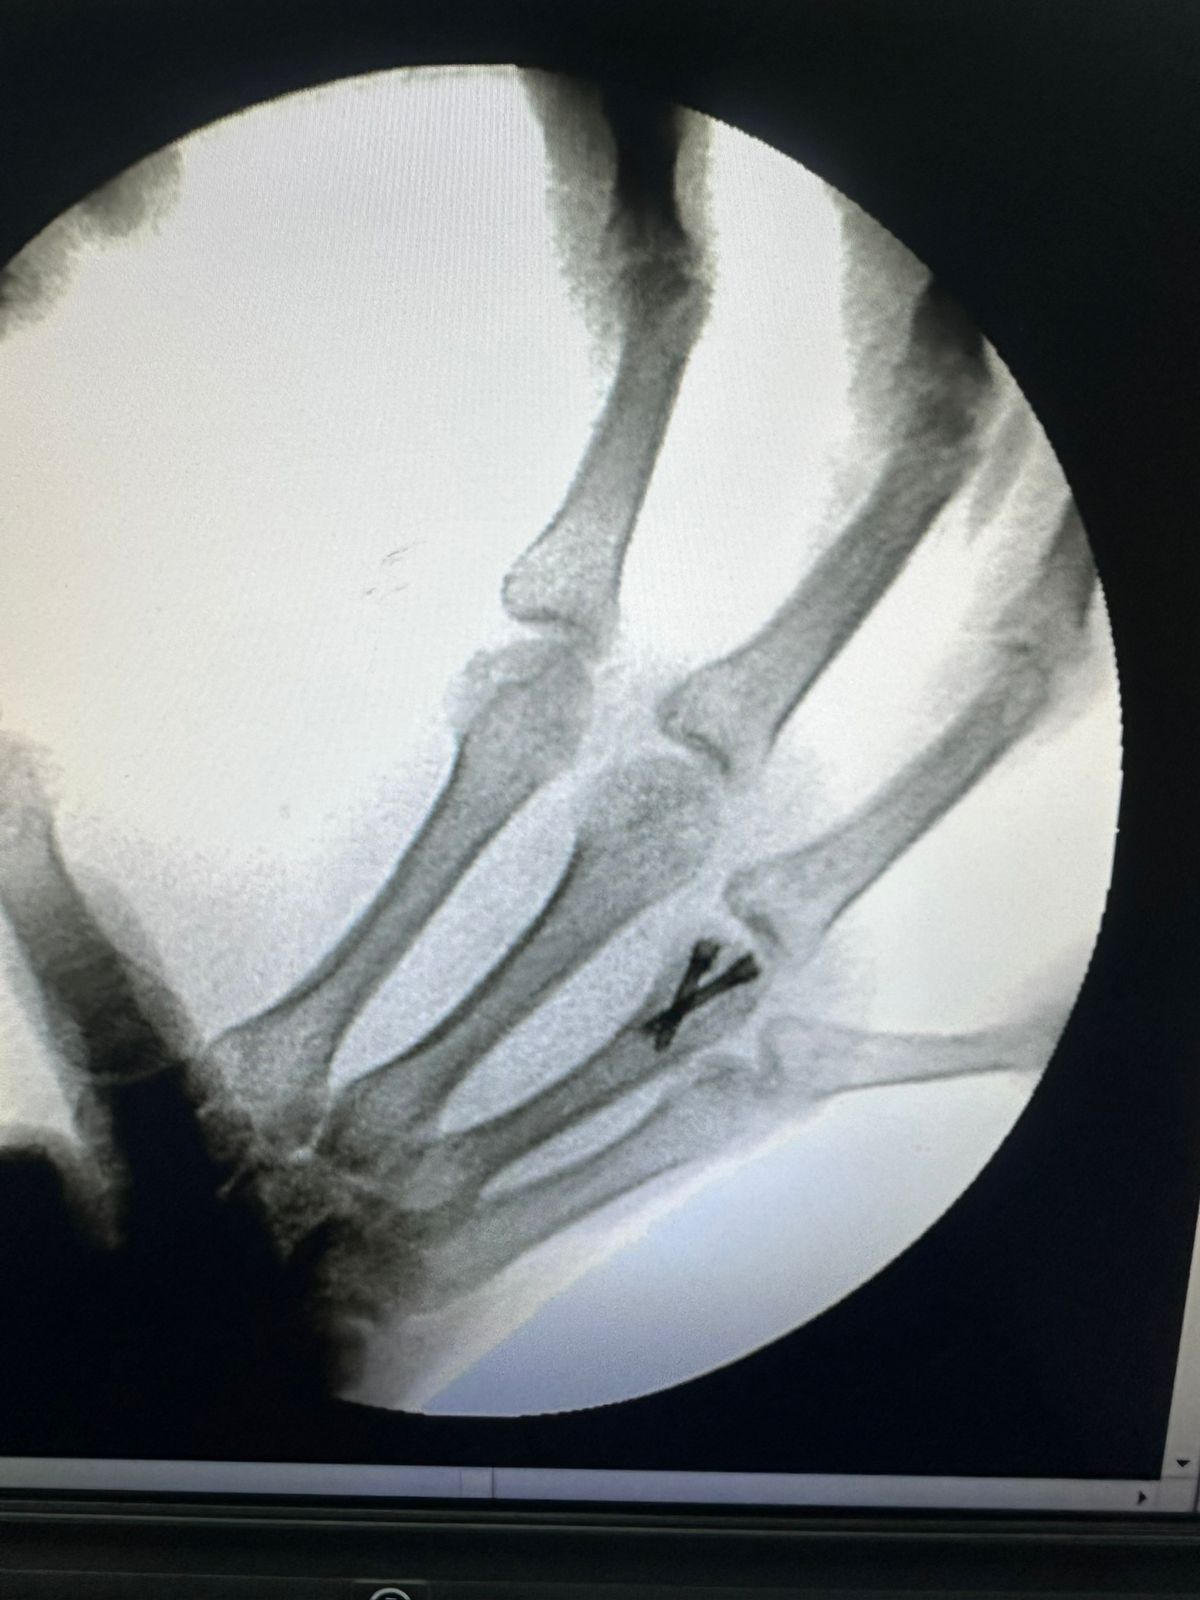

Moments That Mark Meaningful Recovery

Witness real patient transformations at The Ortho Clinic through images that reflect successful treatments and restored mobility.